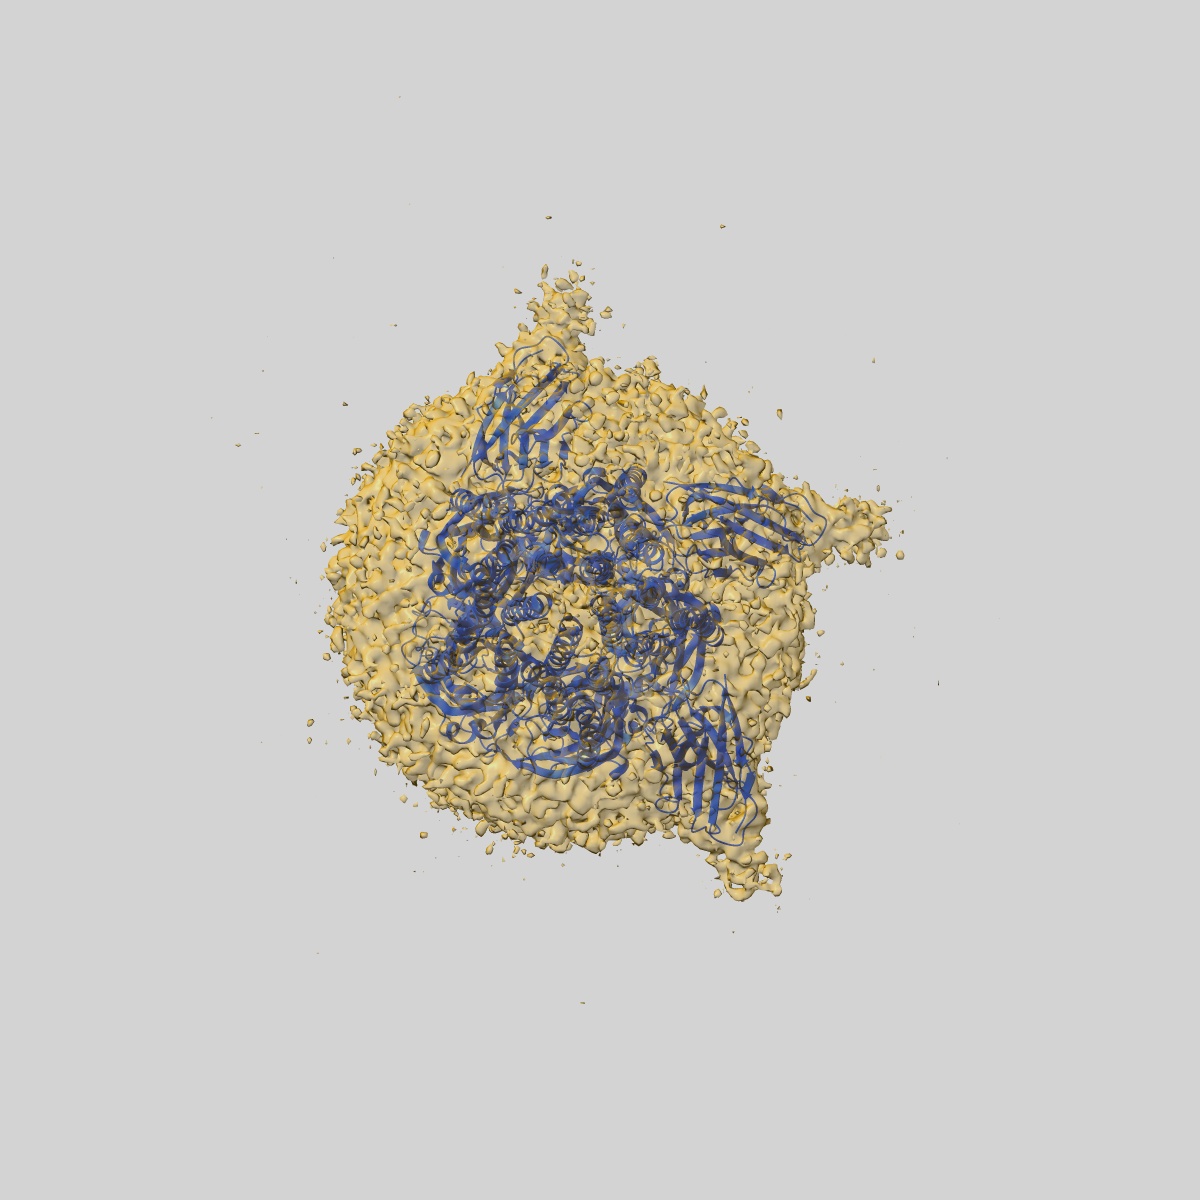

Cryo-EM structure of human full-length beta3delta GABA(A)R in complex with histamine and nanobody Nb25

Single-particle3.1 Å

Sample: Human full-length beta3delta GABA(A)R in complex with histamine and nanobody Nb25

Fitted models: 7qn8